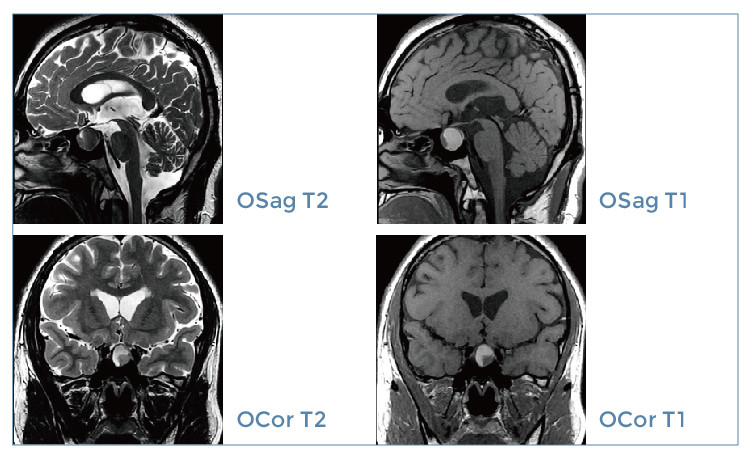

【朗润影像档案】磁共振影像病例分享(编号20191122)